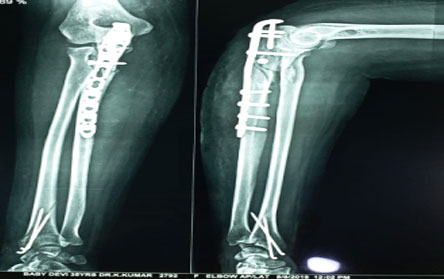

Trauma surgery:

Trauma surgery is a surgical specialty that utilizes both operative and non-operative management to treat traumatic injuries.

The Center of Orthopedics KUMAR ORTHO HOSPITAL ,Patna, offers the entire spectrum of modern orthopedic management, which is effective, patient - friendly & result oriented. In a nutshell, it is one stop treatment for all orthopedic ailments and fractures with emphasis on avoidance of complications, rapid mobilization, decreased period of confinement and an early return to normalcy.